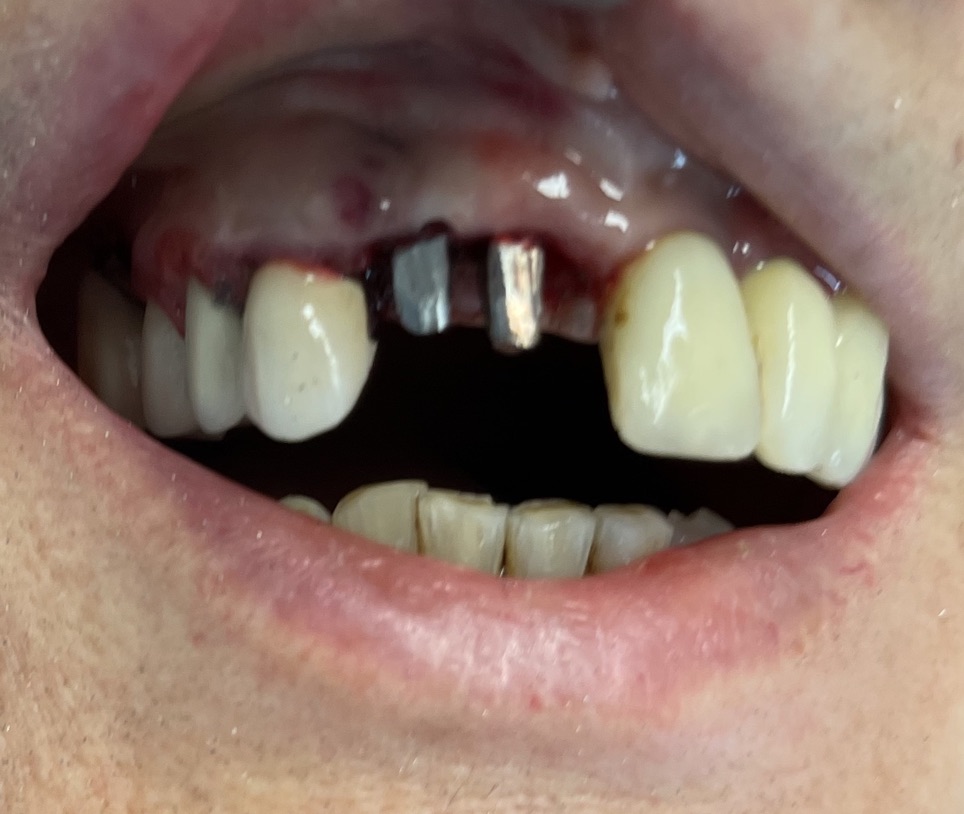

Zona dentale: 11 12

Situazione estrattiva: postestrattivi immediati

Altezza di masticazione alta media bassa: bassa morso profondo

Carico occlusale : immediato leggero

Descrizione intervento

Complicanze: assenti